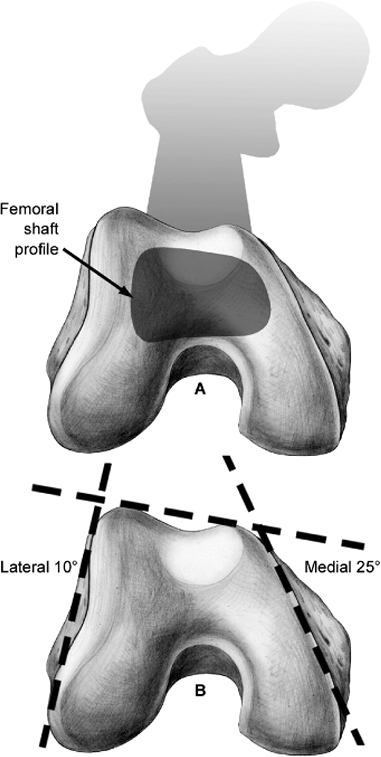

considering a fixation strategy. The distal femur is trapezoidal when

viewed from distal to proximal. The lateral metaphyseal surface is

angulated approximately 10 degrees while the medial side surface is

angulated approximately 25 degrees (Fig. 23.2).

This combination contributes to the widening of the condyles

posteriorly relative to their anterior width. The lateral condyle

extends farther anteriorly relative to the medial condyle, producing a

posterior slope between the anterior condylar prominences when viewed

from lateral to medial. The distal extent of the intercondylar

articular surface is best appreciated on the lateral radiograph, which

can be useful for determining the safe placement of implants during

fixation. The central axis of the femoral shaft normally aligns with

the anterior half of the femoral condyles as viewed laterally. This

alignment is especially important to assess by surgeons considering the

accurate placement of lateral plate constructs.

Figure 23.2.

The distal femoral anatomy as it relates to plate applications. The lateral metaphysis is angulated 10 degrees from the sagittal plane; the medial metaphysis is angulated 25 degrees from the sagittal plane. To avoid a medial translational deformity of the articular surface, lateral plate applications should follow the sloped, lateral, metaphyseal surface. To ensure that screws are contained within the distal femur, the anterior location of the metaphysis must be appreciated. Anterior implants are shorter than those angulated or placed more posteriorly. |